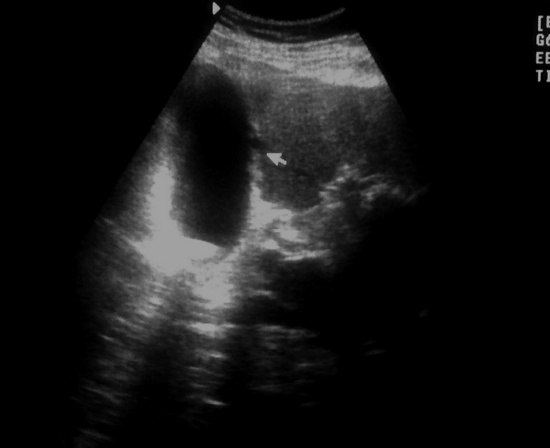

УЗИ ЖКБ.Острый гангренозный холецистит.

Мужчина 68лет, жалобы на боли в правом подреберье:

Через 2 дня боли уменьшились, но появилась Т38,4:

Желчный пузырь с неравномерно утолщённой стенкой на всём протяжении . Дифференцировка слоёв отсутствует ...

Диагноз подтвержден "операционно"...

перивезукулярный абсцесс...

Таки, наверное, да, только скопление жидкости , скорее всё - таки паравезикальноSerg писал(а):острый холецисти с перфорацией, определяется дефект стенки и скопление жидкости в паренхиме печени

Да, все верно. Только в просвете еще и конкременты (может снимок не совсем удачный, больше хотелось вывести "дырку" в стенке, а не камень, но он был

Кстати нарушение целостности видно и здесь: Послеоперационный диагноз (списала с истории болезни): ЖКБ.Острый калькулезный гангренозный холецистит. Перфорация желчного пузыря. Местный перитонит.